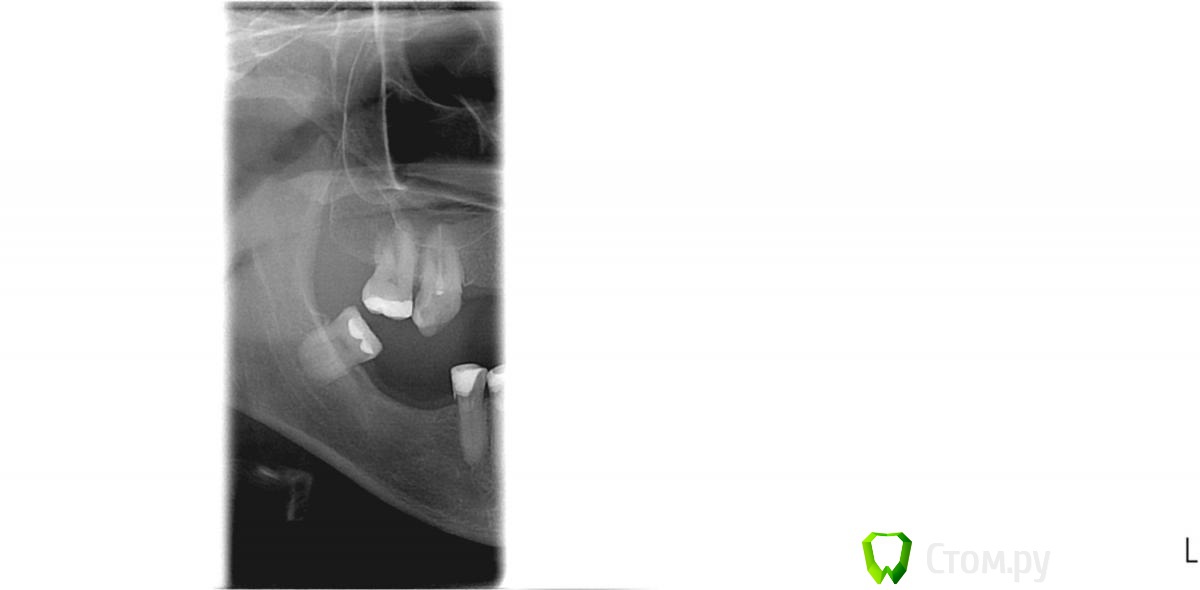

eliseev Опубликовано 5 октября, 2014 Поделиться Опубликовано 5 октября, 2014 (изменено) Здравствуйте.Как мне кажется проблема в восьмерке с правой стороны. Сильно болит зуб, с правой стороны, чаще ночью. Ноющая боль, отдает в висок и в ухо. Врач говорит, что с зубом все нормально. На снимок не посылала. А зуб все равно болит и надо же с этим что-то делать, проявил инициативу и сам сходил на ортопантомограмму. Планировал сделал томограмму всей челюсти, но врач порссоветовал сделать фото только тех зубов которые болят. Изменено 5 октября, 2014 пользователем eliseev Ссылка на комментарий

eliseev Опубликовано 5 октября, 2014 Автор Поделиться Опубликовано 5 октября, 2014 (изменено) Выложите орто.А наверху часть снимка это разве не ортопантомограамма? Просто когда я пришел делать, мне сказали, что снимок всей челюсти делать не нужно, только зубы которые болят.Вот этот снимок и сделали. Изменено 5 октября, 2014 пользователем eliseev Ссылка на комментарий

anvladd Опубликовано 5 октября, 2014 Поделиться Опубликовано 5 октября, 2014 Желательно полный снимок посмотреть, этот не дает полной информации. Ссылка на комментарий

Stomart Опубликовано 6 октября, 2014 Поделиться Опубликовано 6 октября, 2014 По этому кусочку есть проблемы в 5-м нижнем и 7-м верхнем зубах. Ссылка на комментарий

eliseev Опубликовано 7 октября, 2014 Автор Поделиться Опубликовано 7 октября, 2014 По этому кусочку есть проблемы в 5-м нижнем и 7-м верхнем зубах.Спасибо за ответ. А там скорее всего, в этих зубах с каналами проблема? Просто эти зубы мне стоматолог лечил две недели назад. Полное орто постараюсь выполнить к пятнице. Ссылка на комментарий

shishok Опубликовано 9 октября, 2014 Поделиться Опубликовано 9 октября, 2014 17 зуб перелечивать каналы,45 проверять на витальность(живой или нет). Ссылка на комментарий

eliseev Опубликовано 11 октября, 2014 Автор Поделиться Опубликовано 11 октября, 2014 (изменено) 17 зуб перелечивать каналы,45 проверять на витальность(живой или нет).Сегодня врач снова сделал два снимка пятерки и безуспешно искал второй канал. Зуб официально считается мертвым, но когда врач тыкает иголками то боль адская. Разве может так зуб без нерва болеть? Каналы,. врач, говорит хорошо пролеченные, запломбированные.Снимок прилагаю.http://s48.radikal.ru/i119/1410/b2/fe29ada1267c.jpg Здравствуйте ! Боли появились после лечения? Боль была до лечения и сохранилась после. Такое ощущение, что все же болит пятый зуб. Когда языком прикосаюсь или когда кусаю им. Ночью боль от зуба ноющая, трудно заснуть. Но не такая как при пульпите, когда "хоть на стенку лезь". Официально в медкарте 5 зуб считается мертвым с хорошо заплобированными каналами. Выше снимок выложил. Изменено 11 октября, 2014 пользователем eliseev Ссылка на комментарий

M@estro Опубликовано 13 октября, 2014 Поделиться Опубликовано 13 октября, 2014 Понял. Спасибо. Жаль конечно зуб удалять, еще лечащий врач говорил, что зуб с виду красивый и хорошо запломбированный. Значит там получается два канала было, а нашли только один. По снимку пломбировочного материала в канале нет вообще. 1 Ссылка на комментарий

Гарриевич Опубликовано 13 октября, 2014 Поделиться Опубликовано 13 октября, 2014 По снимку пломбировочного материала в канале нет вообще. +1, каналы пустые, зуб на удаление 2 Ссылка на комментарий